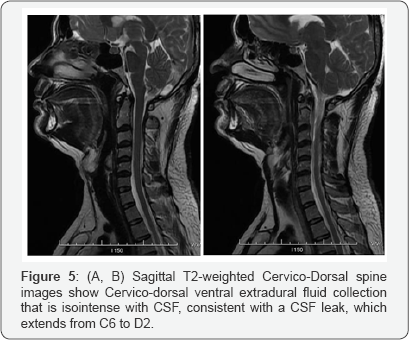

In association with the brain MRI findings, close reexamination of the initial Non contrast spine MRI revealed distension of the cervical epidural veins and epidural fluid collection at the cervico-thoracic junction (Figure 5A & 5B), consistent with a CSF leak in that region. The diagnosis of SIH was made on the basis of typical headache symptoms, low CSF pressure and characteristic MRI findings.